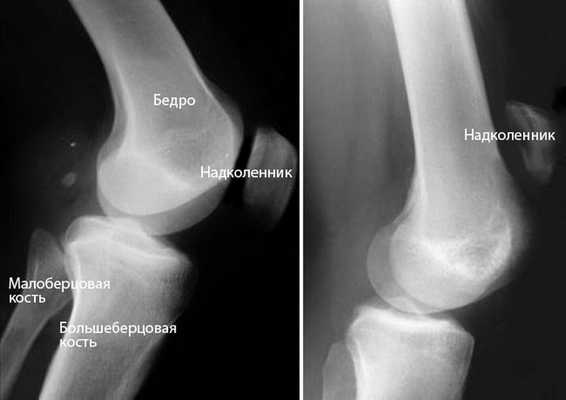

Рентгенография. При рентгенографии, в случае частичного разрыва или полного разделения связки на 2 отдельных фрагмента, наблюдается смещение коленной чашечки по направлению вверх.

Рис 4. (Слева) Боковая проекция показывает нормальное размещение коленной чашечки. (Справа) Смещение связки вверх при ее разрыве.